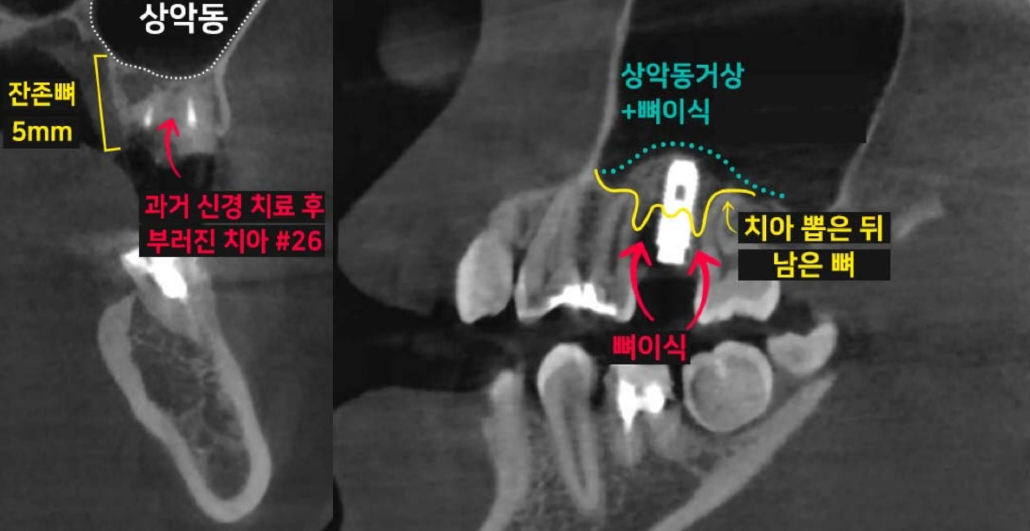

치아 손상으로 발치를 해야 할 때, '과연 바로 임플란트 시술이 가능할까?' 걱정하시는 분들이 많습니다. 이백점치과는 최신 의학 기술과 풍부한 임상 경험을 바탕으로 발치와 동시에 임플란트를 식립하는 것은 물론, 복잡한 케이스까지 성공적으로 진행하여 환자분들의 치료 기간과 불편함을 최소화하고 있습니다. ✨발치 동시 임플란트, 무엇이 다를까요? •일반적인 임플란트 식립: 치아를 발치한 후 잇몸과 뼈가 완전히 아물 때까지 약 3~4개월을 기다린 뒤 임플란트 를 식립합니다. 이후 임플란트와 뼈가 유착되는 데 3~4개월이 추가로 소요되며, 그 후에야 최종 보철물로 식사가 가능해집니다.  이 경우 치아가 없는 상태로 지내는 기간이 길어져 불편함을 느낄 수 있습니다. •이백점치과의 발치 동시 임플란트: 발치와 동시에 임플란트를 식립함으로써 치료 단계를 줄이고, 임플란트가 뼈와 유착되는 3~4개월 후에는 바로 최종 보철물(크라운)을 올려 즉시 식사가 가능합니다.  이를 통해 전체 치료 기간과 환자분의 불편감을 획기적으로 줄일 수 있습니다. CASE. 30대 여성 환자"이가 부러졌어요" ○ 환자분의 고민: 왼쪽 위 치아가 부러지고 염증이 생겨 임플란트를 희망하며 내원하셨습니다. ○ 진단: 파노라마와 CT 촬영 결과, 치아 뿌리만 남아있는 상태였고, 더 이상 치아를 살릴 수 없어 발치가 필요했습니다. 임플란트를 심을 수 있는 뼈가 5mm 정도로 부족하여, 일반적인 길이의 임플란트 식립을 위해 상악동거상술(뼈이식)이 동반되어야 하는 고난이도 케이스였습니다. ○ 치료 계획: 발치 후 즉시 임플란트 식립 & 상악동거상술 및 뼈이식 동시 진행 ![]() 이백점치과의 정교한 발치 동시 임플란트 과정 과거에는 치아를 뽑고 3~4개월을 기다려야 임플란트 식립이 가능하다고 알려져 있었습니다. 하지만 이백점치과 는 다음과 같은 정교한 술식을 통해 발치와 동시에 임플란트 식립 및 뼈이식까지 가능하게 합니다. 1. 정확한 발치: 기존 뼈를 최대한 보존하며 잔존 치근과 치근단 염증을 완벽하게 제거합니다. 2. 이상적인 임플란트 식립: 환자분의 교합과 잔존 뼈를 고려하여 가장 이상적인 위치와 각도로 임플란트를 식립합니다. 3. 동시 뼈이식 및 상악동 거상술: 뼈가 부족한 부위에는 충분한 뼈이식을 진행하며, 특히 위턱 어금니 부위는 상악동 막을 안전하게 들어 올리는  상악동 거상술을 동시에 시행하여 임플란트가 단단하게 고정될 수 있는 기반을 마련합니다. 4. 깔끔한 잇몸 봉합: 빠르고 안정적인 치유를 위해 섬세하고 정확하게 잇몸을 봉합합니다. ![]() 빠른 회복과 뛰어난 예후: 믿을 수 있는 이백점치과 수술 직후부터 빠른 회복 과정을 보이는 것은 정확한 수술과 봉합 덕분입니다.  3개월 후 파노라마 사진에서도 상악동이 깨끗하고 뼈이식 부위가 자기 뼈로 잘 대체되고 있음을 확인할 수 있었습니다. ![]() 이처럼 발치 후에도 바로 임플란트 식립이 가능하며, 상악동 거상술과 뼈이식까지 동시에 진행될 수 있습니다. 이백점치과는 다양한 임상 경험을 바탕으로 고난이도 케이스도 성공적으로 이끌어내고 있으며, 수술 결과와 예후 로 환자분들께 신뢰를 증명하고 있습니다.  |